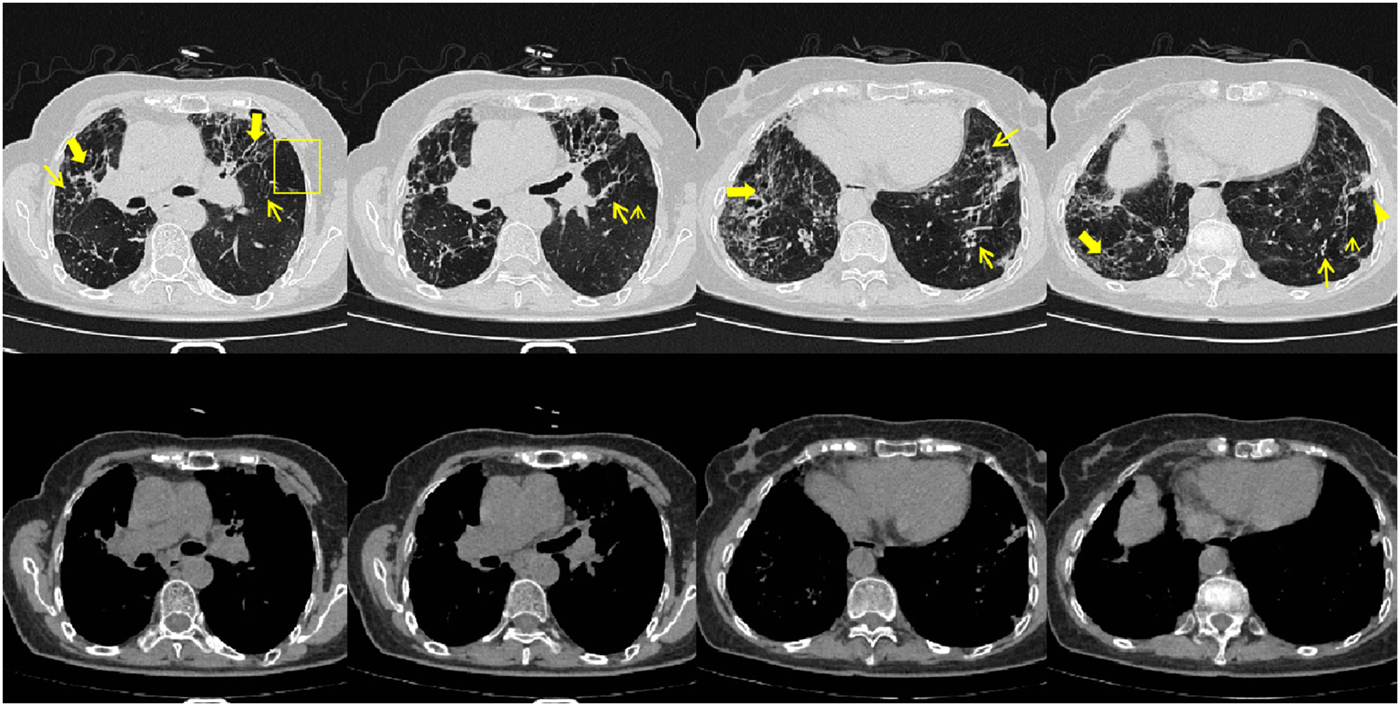

On 26 May 2024, the patient returned to our hospital for further treatment. Chest CT showed multiple bronchiectasis with infection in both lungs and thickening of the bilateral pleura (Figure 2). Laboratory results showed white blood cell count (10.11 × 109/L), absolute eosinophil count (0.34 × 109/L), C-reactive protein (49.89 mg/L), procalcitonin (0.248 ng/mL), and total serum IgE (>2500 U/mL). Fiberoptic bronchoscopy revealed large amounts of jelly-like purulent mucus in the bilateral bronchial lumens, with bronchial mucosa edema and narrowed lumens. In the left upper lobe anterior segmental bronchus, thick jelly-like purulent mucus secretions were seen obstructing the passage. After repeated flushing and suctioning of the mucus plugs, the distal bronchus was patent, and no neoplasms or bleeding were observed (Figure 3). Cuentrifgal precipitate smear of BALF was stained with Raget’s stain, and 45-degree branched septate hyphae were seen under the microscope, and gray-green colonies were seen in the culture, which were consistent with Aspergillus fumigatus (Figure 4). The BALF GM test was 0.13 μg/L, and the tNGS of the BALF reported Aspergillus flavus (1 × 102 copies/mL) and EBV. A. fumigatus-specific IgE was 44.4 kUA·L−1.

FIGURE 2

Patient’s chest CT imaging on 28 May 2024. The chest computed tomography showed bronchiectasis (bold arrows) and chronic pleuropulmonary fibrosis (triangles), with remission of mucus plugging (narrow arrows), bronchopneumonia (arrow heads) and tree-in-bud opacities (yellow boxes) compared to Figure 1, indicating partial remission of ABPA and IPA.